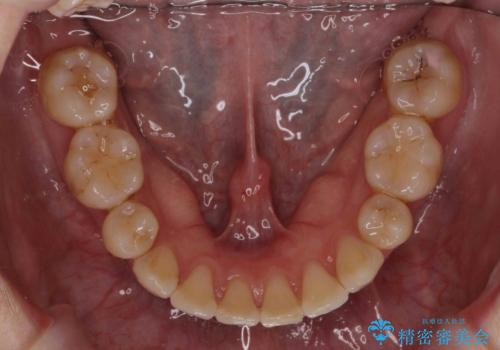

左上の小臼歯が込み合っており、虫歯治療が厳しい状態でした。

矯正治療をおすすめし、ちょうど虫歯がひどい歯は抜歯して前歯を下げました。

下顎の大臼歯が前に倒れこんでいたため、矯正用ミニスクリューで後ろに起こしています。

治療の難易度としてはかなり高めでしたが、無事終了することができました。